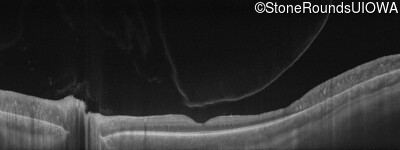

Swept-Source OCT - Right - 20/40 +2 sc

Exemplar

Swept-Source OCT - Left - 20/40 +2 sc